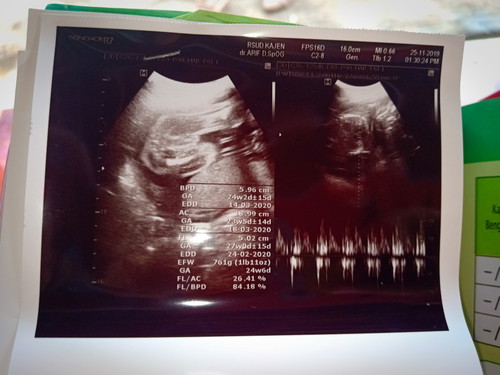

hasil Usg

GA (Gestational Age): menunjukkan perkiraan umur kehamilan Anda, diukur berdasarkan panjang tungkai lengan, tungkai kaki, ataupun diameter kepala, dan mendeteksi perkembangan organ tubuh janin. Jika salah satu dari GA di USG menunjukkan ukuran yang tidak normal, dokter langsung bisa mendeteksinya sebagai kelainan, terutama GA di bagian kepala. • GS (Gestational Sac): yaitu ukuran kantung kehamilan, berupa bulatan hitam. Ini biasanya muncul pada hasil foto USG trimester awal. • CRL (Crown Rump Length): yaitu ukuran jarak dari ujung kepala hingga ujung kaki bayi. Ini juga biasa digunakan dokter untuk mengukur janin di usia kehamilan trimester awal. • BPD (Biparietal Diameter): yaitu ukuran tulang pelipis kiri dan kanan. Biasa digunakan untuk mengukur janin di trimester dua atau tiga. • FL (Femur Length): merupakan ukuran panjang tulang paha bayi. • HC (Head Circumferencial): yaitu ukuran lingkaran kepala • AC (Abdominal Circumferencial): yaitu ukuran lingkar perut bayi. Jika dikombinasikan dengan BPD akan menghasilkan perkiraan berat bayi. • FW (Fetal Weight): yaitu berat janin dalam kandungan. • FHR (Fetal Heart Rate): yaitu frekuensi jantung bayi Sumber : https://www.motherandbaby.co.id/article/2019/2/5/11770/Moms-Yuk-Ketahui-Cara-Membaca-hasil-USG Kl bca sndiri jdinya hplnya bnyak hehe it skilas sy liat ad yg 18 februari, ad yg 24 maret. Bb janinnya kyknya 761 atau 701 g. Untuk lbih jlasnya wkt usg biasanya bsa mnta dijlasin bund hihi.